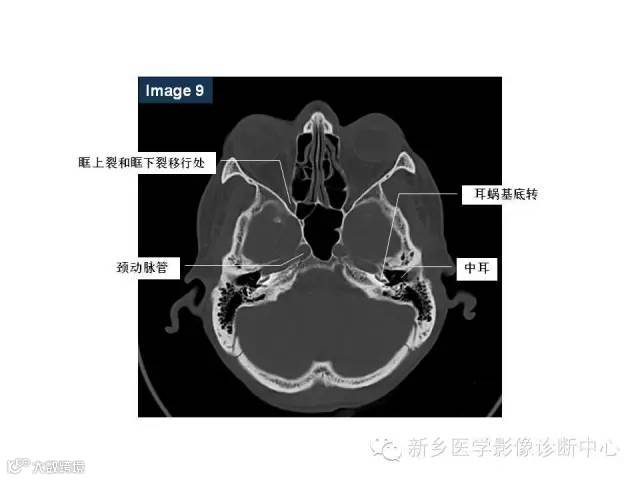

颅底孔道解剖详解

值得收藏!